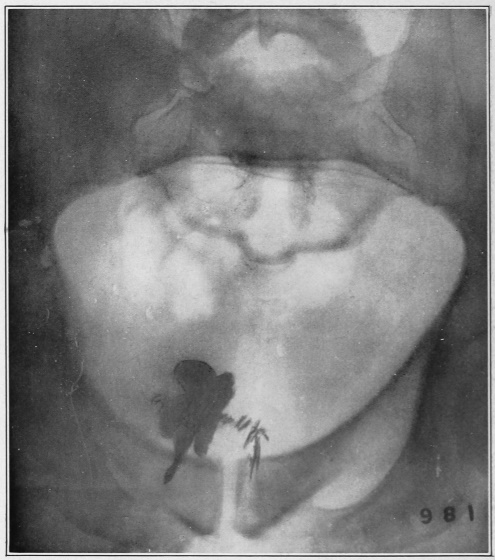

Nine Radiograph Illustrations Showing Mucus Channels and Cavities200

Rebellion of our outraged Internal Economy.